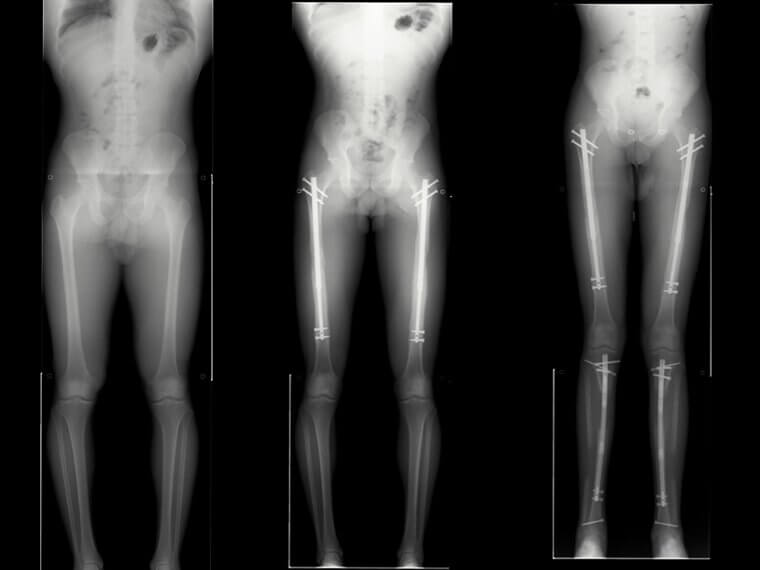

Seis pulgadas m谩s alto, pieza a pieza

Esta serie de radiograf铆as revela el intenso proceso de alargamiento quir煤rgico de la extremidad, en el que ambos f茅mures y tibias fueron cuidadosamente fracturados y estabilizados con clavos de titanio ajustables.

Con el tiempo, los huesos se extienden gradualmente, permitiendo que se forme hueso nuevo y aumentando la estatura en 15 cm mediante un proceso de reconstrucci贸n lento y controlado.